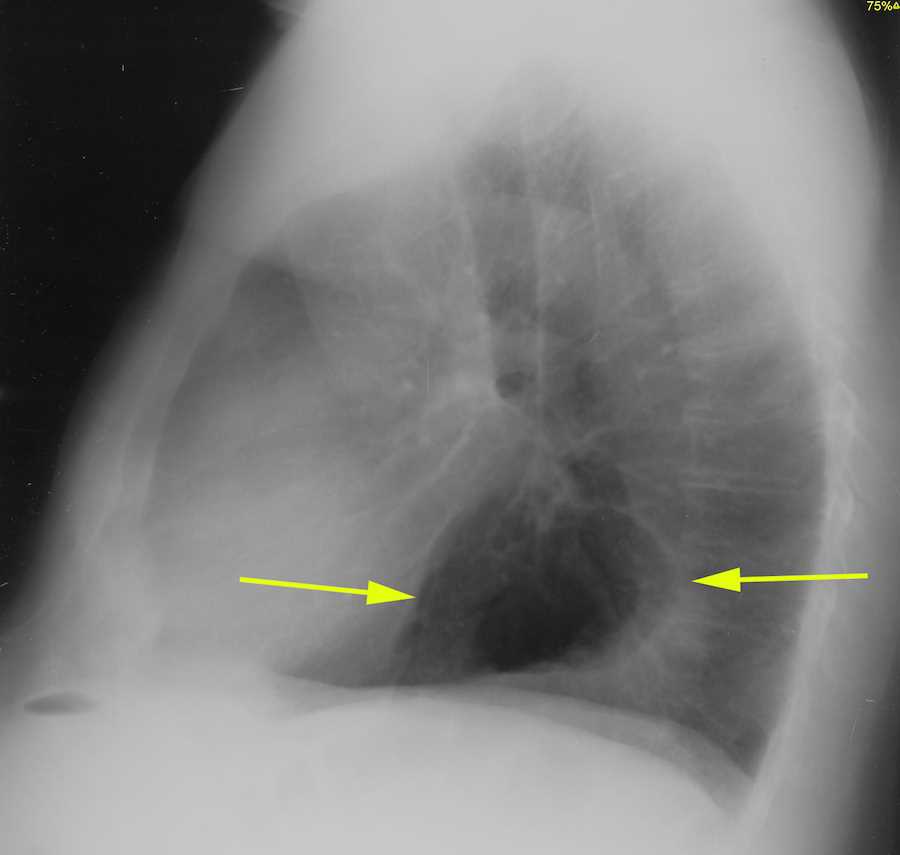

Hiatal Hernia. AP and Lateral Chest Radiograph Annotated. JETem 2018

From jetem.org

Hiatal Hernia. AP and Lateral Chest Radiograph Annotated. JETem 2018 What Does A Chest Xray Show Hiatal Hernia The gastric fundus may also. A hiatal hernia is often discovered during a test or procedure to determine the cause of heartburn or pain in the chest or upper abdomen. Hiatal hernia symptoms may occur as a result of stomach acid or bile. Hiatal hernias happen more often in. An upper gi barium series is the preferred examination in the. What Does A Chest Xray Show Hiatal Hernia.